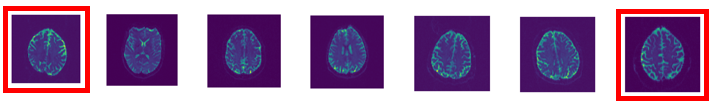

V-C Autoencoder compression for MRI brain scans

Experiment 4 (MRI compression).

We consider the MRI brain scans dataset from Open Access Series of Imaging Studies (OASIS) [72]. We extract two-dimensional slices from the three-dimensional MRI images, resulting in images of resolution -pixels. We follow Experiment 3 by splitting the dataset into training images and complementary test images and compare the AE compression for latent dimension . Results for latent dimension and training data are given in the supplements, as well as further details on the specifications.

We keep the architecture setup of the AEs, but increase the NN sizes to hidden layers each consisting of neurons. Reconstructions measured by PSNR are evaluated in Fig. 24, Fig. 25. Analogous results apper for SSIM, see the supplements.

As in Experiment 3 we observe that AE-REG and Hybrid AE-REG perform compatible or slightly worse than the other AEs in the unperturbed scenario, but show their superiority over the other AEs for Gaussian noise, or for CNN-VAE. Especially Hybrid AE-REG maintains its reconstruction quality under noise perturbations up to (maintains stable for ). The performance increase compared to the un-regularised MLP-AE becomes evident and validates again that a strong robustness is achieved due to the regularisation.

A show case is given in Fig. 23. Apart from Hybrid AE-REG (row (8)) all AEs show artefacts when reconstructing perturbed images. CNN-VAE (row (4)) and AE-REG (row (7)) perform compatible and maintain stable up to Gaussian noise perturbation.

In Fig. 26-31 examples of geodesics are visualised, being computed analogously as in Experiment 3 for the encoded images once without noise and once by adding Gaussian noise before encoding. The AE-REG geodesic consists of similar slices, including one differing slice for Gaussian noise perturbation. CNN-VAE delivers a shorter path, however includes a strongly differing slice, which is kept for of Gaussian noise. CNN-AE provides a feasible geodesic in the unperturbed case, however becomes unstable in the perturbed case.

We interpret the difference of the AE-REG to CNN-VAE and CNN-AE as an indicator for delivering consistent latent representations on a higher resolution. While the CNN-AE and AE-REG geodesics indicate that one may trust the encoded latent representations, the CNN-AE encoding may not be suitable for reliable post-processing, such as classification tasks. More show cases are given in the supplements, showing similar unstable behaviour of the other AEs.

Summarising, the results validate once more regularisation and hybridisation to deliver reliable AEs that are capable for compressing real world datasets to low dimensional latent spaces by preserving their topology. How to extend the hybridisation technique to images or datasets of high resolution is one of the aspects we discuss in our concluding thoughts.